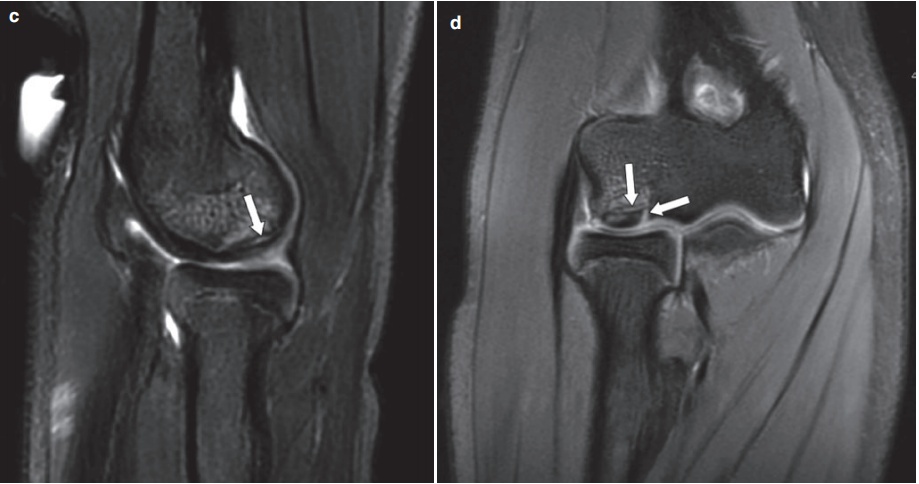

对于一些软组织的显示,尤其是骨折周围韧带、肌肉以及软骨的损伤程度,MRI有显著的优势。比如这位外伤病人,他的MRI图像能明确地诊断剥脱性骨软骨损伤。

(同一患者的X线片与MRI图)